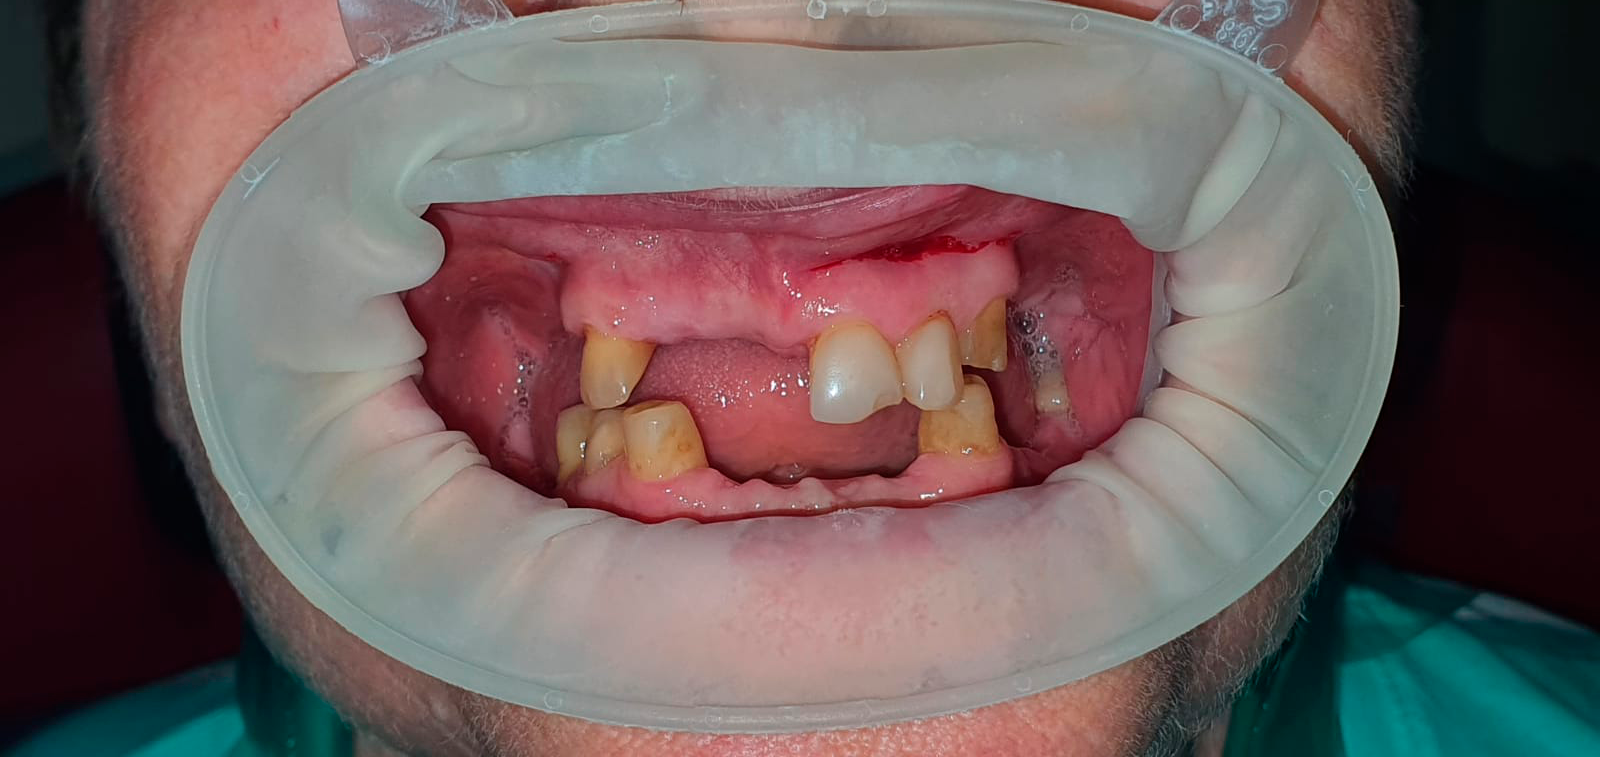

Временные композитные реставрации. Промежуточный этап в ортопедическом лечении. Выполнил врач Краснов Д.А.

До

После